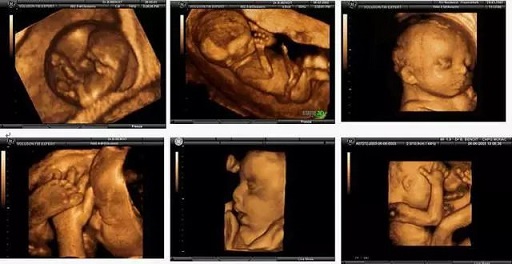

• 為何四維彩超如此受孕媽歡迎

為何四維彩超如此受孕媽歡迎

孕媽正在長沙百佳瑪麗亞婦產(chǎn)醫(yī)院做四維彩超?! ∷木S彩超這項(xiàng)孕期必檢項(xiàng)目孕媽圈無人不知,之所以能在產(chǎn)檢項(xiàng)目中脫穎而出,不僅因?yàn)樗蚱屏藗鹘y(tǒng)B超黑白圖像的沉悶,更重要

寶寶的第一張照片:四維彩超,孕媽媽們了解一下吧

親貝網(wǎng)小編了解到,懷孕以后,準(zhǔn)媽媽都很關(guān)心腹中胎兒的發(fā)育情況,每當(dāng)看到其他準(zhǔn)媽媽曬的胎兒四維彩超的照片和錄像,心都要被萌化了,也想做一次四維彩超。那么有關(guān)四維彩超的知識(shí),你知道嗎,一起來了解一下吧。

孕檢必須要做四維嗎?結(jié)果可能讓你想不到

普通B超拍的是黑白圖片,彩超拍的是彩色照片,三維彩超是給彩色圖片做了3D建模,四維彩超則是在3D建模的基礎(chǔ)上加了動(dòng)畫特效。總而言之,普通B超和彩超的區(qū)別,就是黑白照片和彩色照片的區(qū)別。彩超應(yīng)用廣泛,是因?yàn)楦菀卓辞逄河袥]有出現(xiàn)臍帶繞頸。